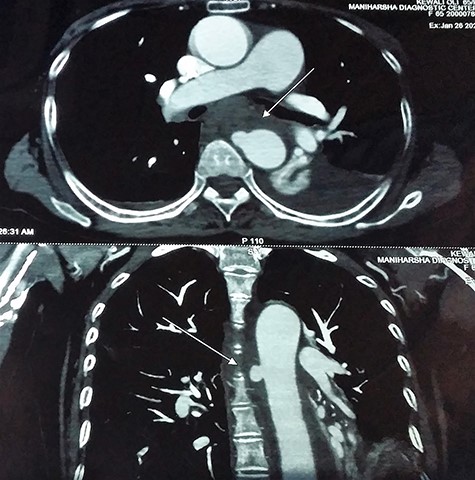

Contrast-enhanced chest computed tomography (CE-CT) with thoracic and abdominal aortogram showed a saccular aneurysm arising from the right lateral wall of the proximal descending thoracic aorta (10 × 8 mm, neck 8 mm) with peri-aneurysmal hematoma tracking along the left posterior mediastinum, causing anterior displacement of the esophagus and a left-sided hemothorax suggestive of a ruptured aneurysm (Figs 2 and 3).

CE-CT image showing saccular aneurysm arising from the proximal descending thoracic aorta.